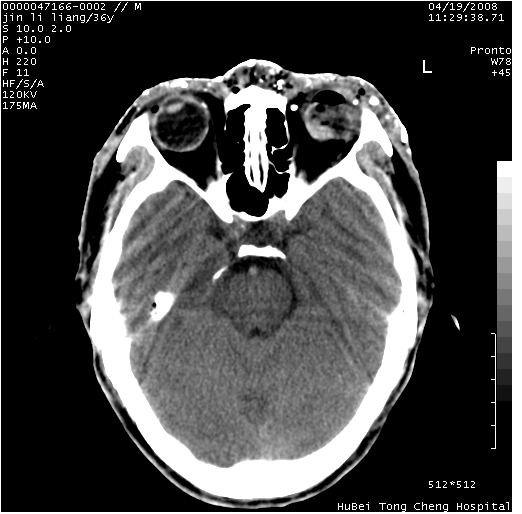

患者 男,36岁。头面部“土炮”炸伤。pe:面目全非,伤口流血不止。

临床诊断:头面部外伤。

颅脑ct轴位平扫(层厚、层距均为10mm),图像如下:

左眼球内容物浑浊其内见气体影,头面部异物.

左眼球破裂并异物,眶周、额顶部头皮及软组织挫伤并异物

左眼球破裂积气并异物,眶周、额顶部头皮及软组织挫伤并异物!

迎面一炮,满脸开曝。额顶部头皮及软组织挫伤并异物,左眼球破裂积气并异物,典型的面目全非,惨不忍睹。

左眼球破裂积气并异物,眶周、额顶部头皮及软组织挫伤并异物,右侧眼环前内分异物

1左侧眼球破裂并积气,球内、框内异物。

2额部顶部软组织伤。